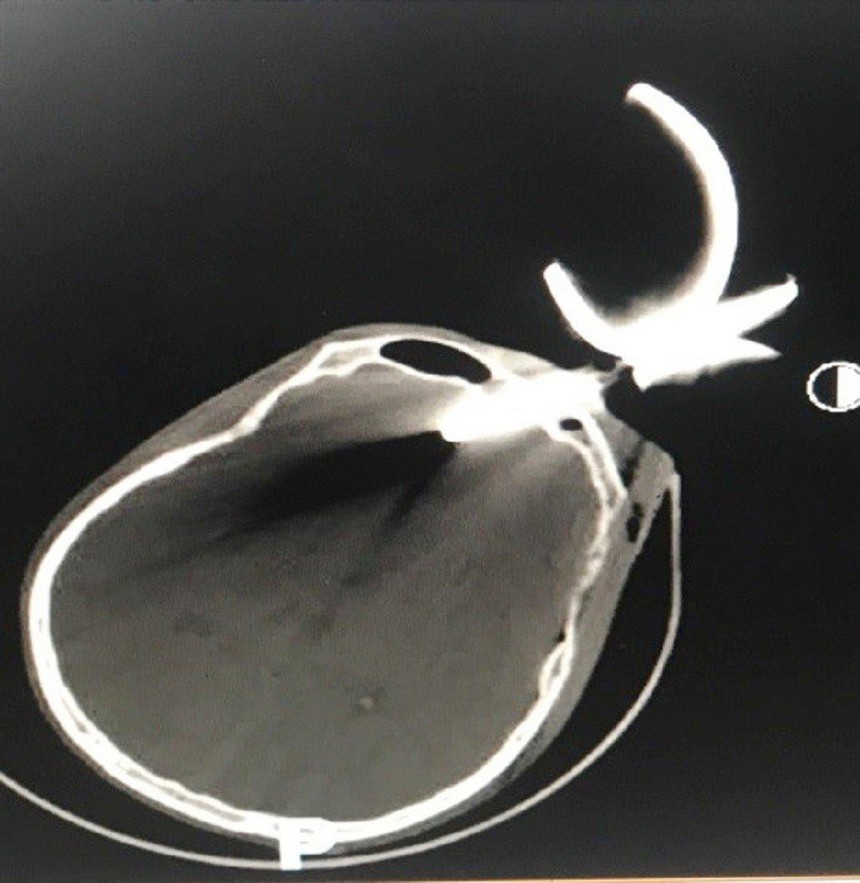

Phim X-Quang của nạn nhân trước khi tiến hành phâu thuật. Ảnh: TTXVN phát

Bác sĩ Ngô Nguyên Quang, Phó Trưởng Khoa Ngoại thần kinh, Bệnh viện Nhân dân 115 cho biết, thời điểm được chuyển đến Khoa Cấp cứu, người đàn ông này bị một dị vật kim loại cắm chặt vào sọ ở vùng trán giữa. Nhìn từ bên ngoài, dị vật là một phần của bông cửa sắt hàng rào bị gãy. Người bệnh tiếp xúc chậm, chân tay còn tự cử động được. Ngay lập tức, các bác sĩ đã khẩn trương chụp CT-Scan sọ não. Kết quả kiểm tra hình ảnh cho thấy, dị vật đã đâm xuyên xương sọ vào nhu mô não trán, độ sâu vết thương khoảng 4 cm, vị trí ngay cực trán. Tình trạng trên khiến bệnh nhân đối mặt với nguy cơ tử vong rất cao.